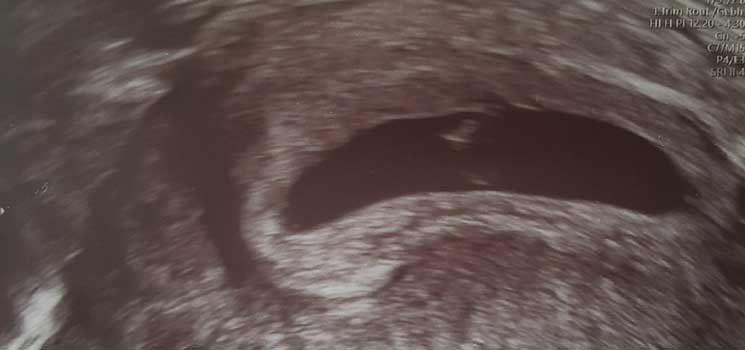

Unerwartet, aber dennoch sehr Willkommen - Tagebücher aus der Schwangerschaft von Leandra aus Lübeck